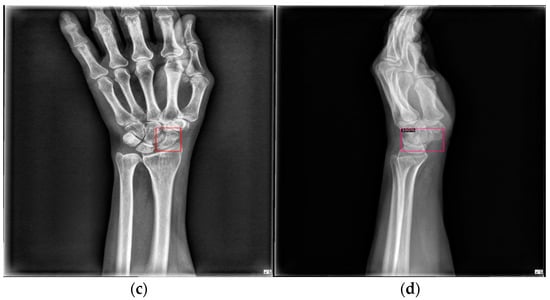

Figure 9 shows the results of scaphoid fracture detection. In the figure, the red area represents the ground-truth box labeled by the doctor, while the green area shows the result predicted by the model. Figure 10 provides an example of a more obvious fracture, whereas Figure 11 illustrates an example of an occult fracture. These examples highlight the challenges in diagnosing scaphoid fractures, as occult fractures are difficult to distinguish by the naked eye. The AP views demonstrate a relatively high IoU, while the LA views also accurately locate the fracture area. This combined approach is effective in drawing the doctor’s attention to the area, enabling quicker identification of the fracture location.

Figure 9.

Scaphoid detection visualization. (a–d) The AP and LA views of the same patient. The first row is the ground truth, and the second row is the predicted result.

Figure 10.

Fracture detection visualization. (a,b) Scaphoid bone slices. The red box is the true answer, and the green box is the predicted result.